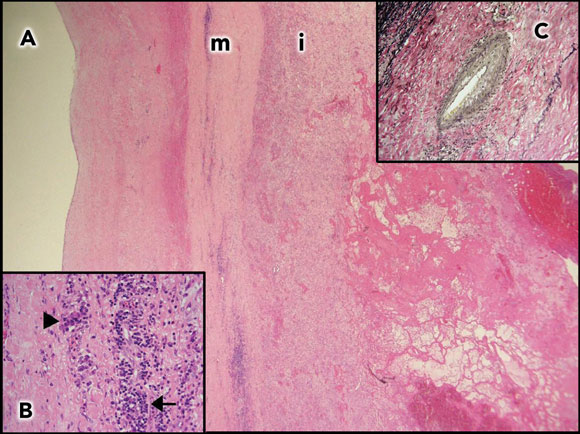

She had an aortic valve replacement, and replacement of the ascending aorta with a synthetic graft. Macroscopically, the aortic wall was extremely thick. Histological sections showed features consistent with syphilitic aortitis (Figure 1). Her recovery was slow, but she is now living independently 15 months after surgery.

1 Aortic wall of Patient 1  A: Aortic wall (2 x objective) with thickened media (m) and intima (i). |